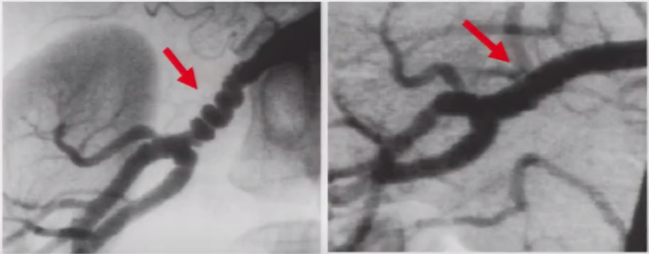

➤ 中膜纤维组织增生的典型表现——串珠样狭窄改变

图7 55岁女性,表现为难以控制的高血压,肾动脉和颈内动脉中-远段呈串珠样狭窄改变,串珠直径大于正常血管腔